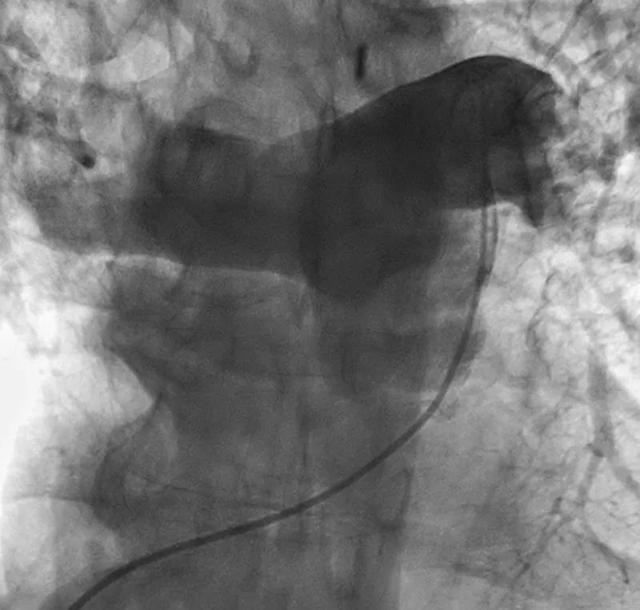

给予肝素、替格瑞洛、阿司匹林、血管加压药和气管插管治疗。D-二聚体>20000 ng/ml。急诊冠脉造影显示非阻塞性病变。肺动脉造影显示双侧肺血栓栓塞,左肺动脉完全闭塞,右肺动脉次全闭塞,如图2。

图2 肺血管造影(前后位)显示左肺动脉完全闭塞,右肺动脉次全闭塞,主肺动脉和双侧肺动脉有较大的充盈缺损